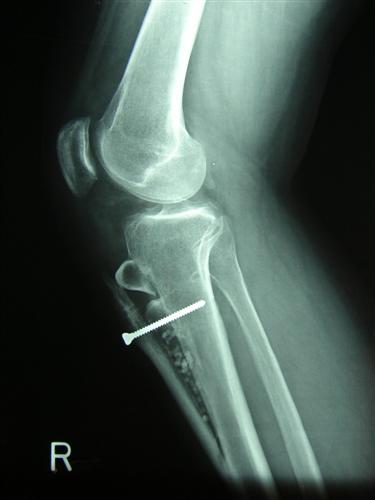

Oblique tibial tubercle osteotomy

When isolated patello-femoral osteoarthrosis involves mainly the lateral facet of the patella, and is associated with lateral tethering of the patella, leading to tilt and/or subluxation, an oblique osteotomy of the tibial tubercle ('Fulkerson osteotomy') can be considered. This involves an oblique saw cut through the tibia, to move the attachment of the patellar tendon forward (anteriorly) and inward (medially). The rationale for this procedure is to re-align the patella into the middle of the femoral groove, while diminishing the forces going through the joint surfaces by moving the tendon attachment forward.

This is a fairly involved procedure. Afterward, the cut surfaces have to heal together again, usually in 6-8 weeks. Limited weightbearing during this period may be necessary for protection of the repair.

Some improvement can be expected reasonably consistently, but pain relief may very well remain incomplete.

Post-operative X-ray after oblique tibial tubercle osteotomy.